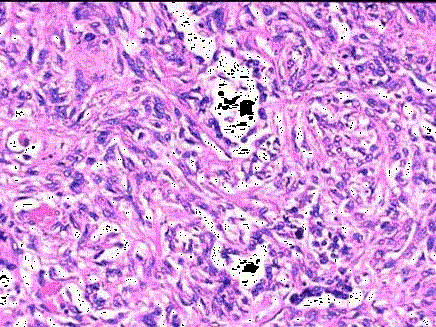

问题 老年男性,曾是一名石棉矿矿工,尸检见胸膜腔内有一肿块,约5cm×4cm×3cm大小,如图所示,应首先考虑的诊断为 ( )

选项 A.胸膜斑 B.胸腺转移瘤 C.毛细血管内皮瘤 D.恶性胸膜间皮瘤 E.恶性淋巴瘤

答案 D